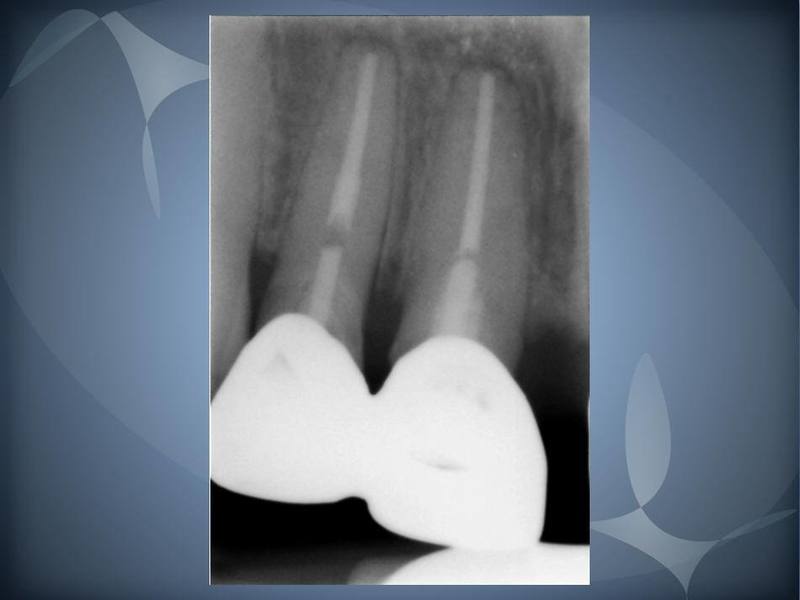

Root Canal Treatment Thru Dental Crowns St. Lawrence Dentistry Dental Crown Radiograph Explain, radiographically, why dental tissues and materials. The film shows the entire crown and root of the teeth which provides vital. Periapical radiographs provide important information about the teeth and surrounding bone. Although artifacts caused by metal restorations (amalgam restorations, crowns, and bridges) in conventional imaging are extremely infrequent, even in panoramic radiography. Crowned dens syndrome is an inflammatory condition. Dental Crown Radiograph.